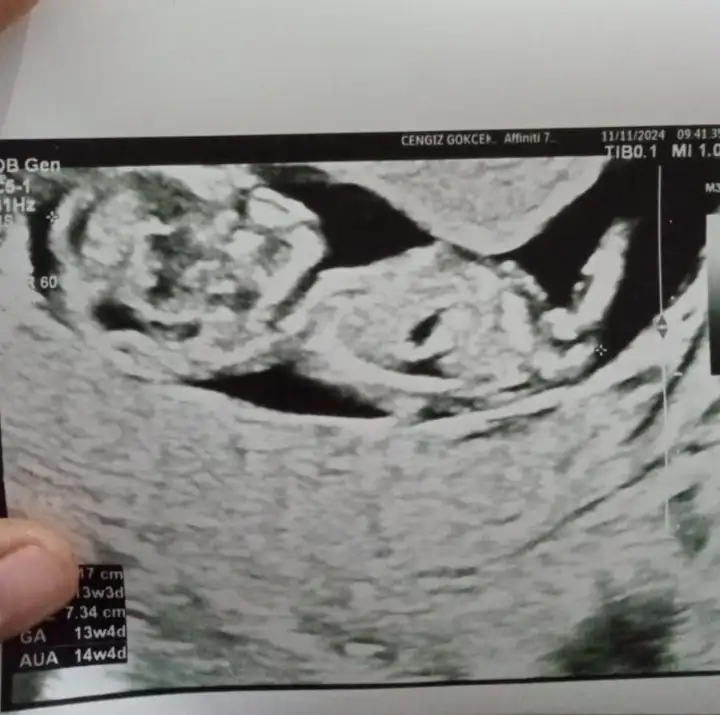

Çok merak ediyorum cinsiyet tahmini yapar mısınız rica etsem

13 haftalık cinsiyet tahmini yapabilir misiniz